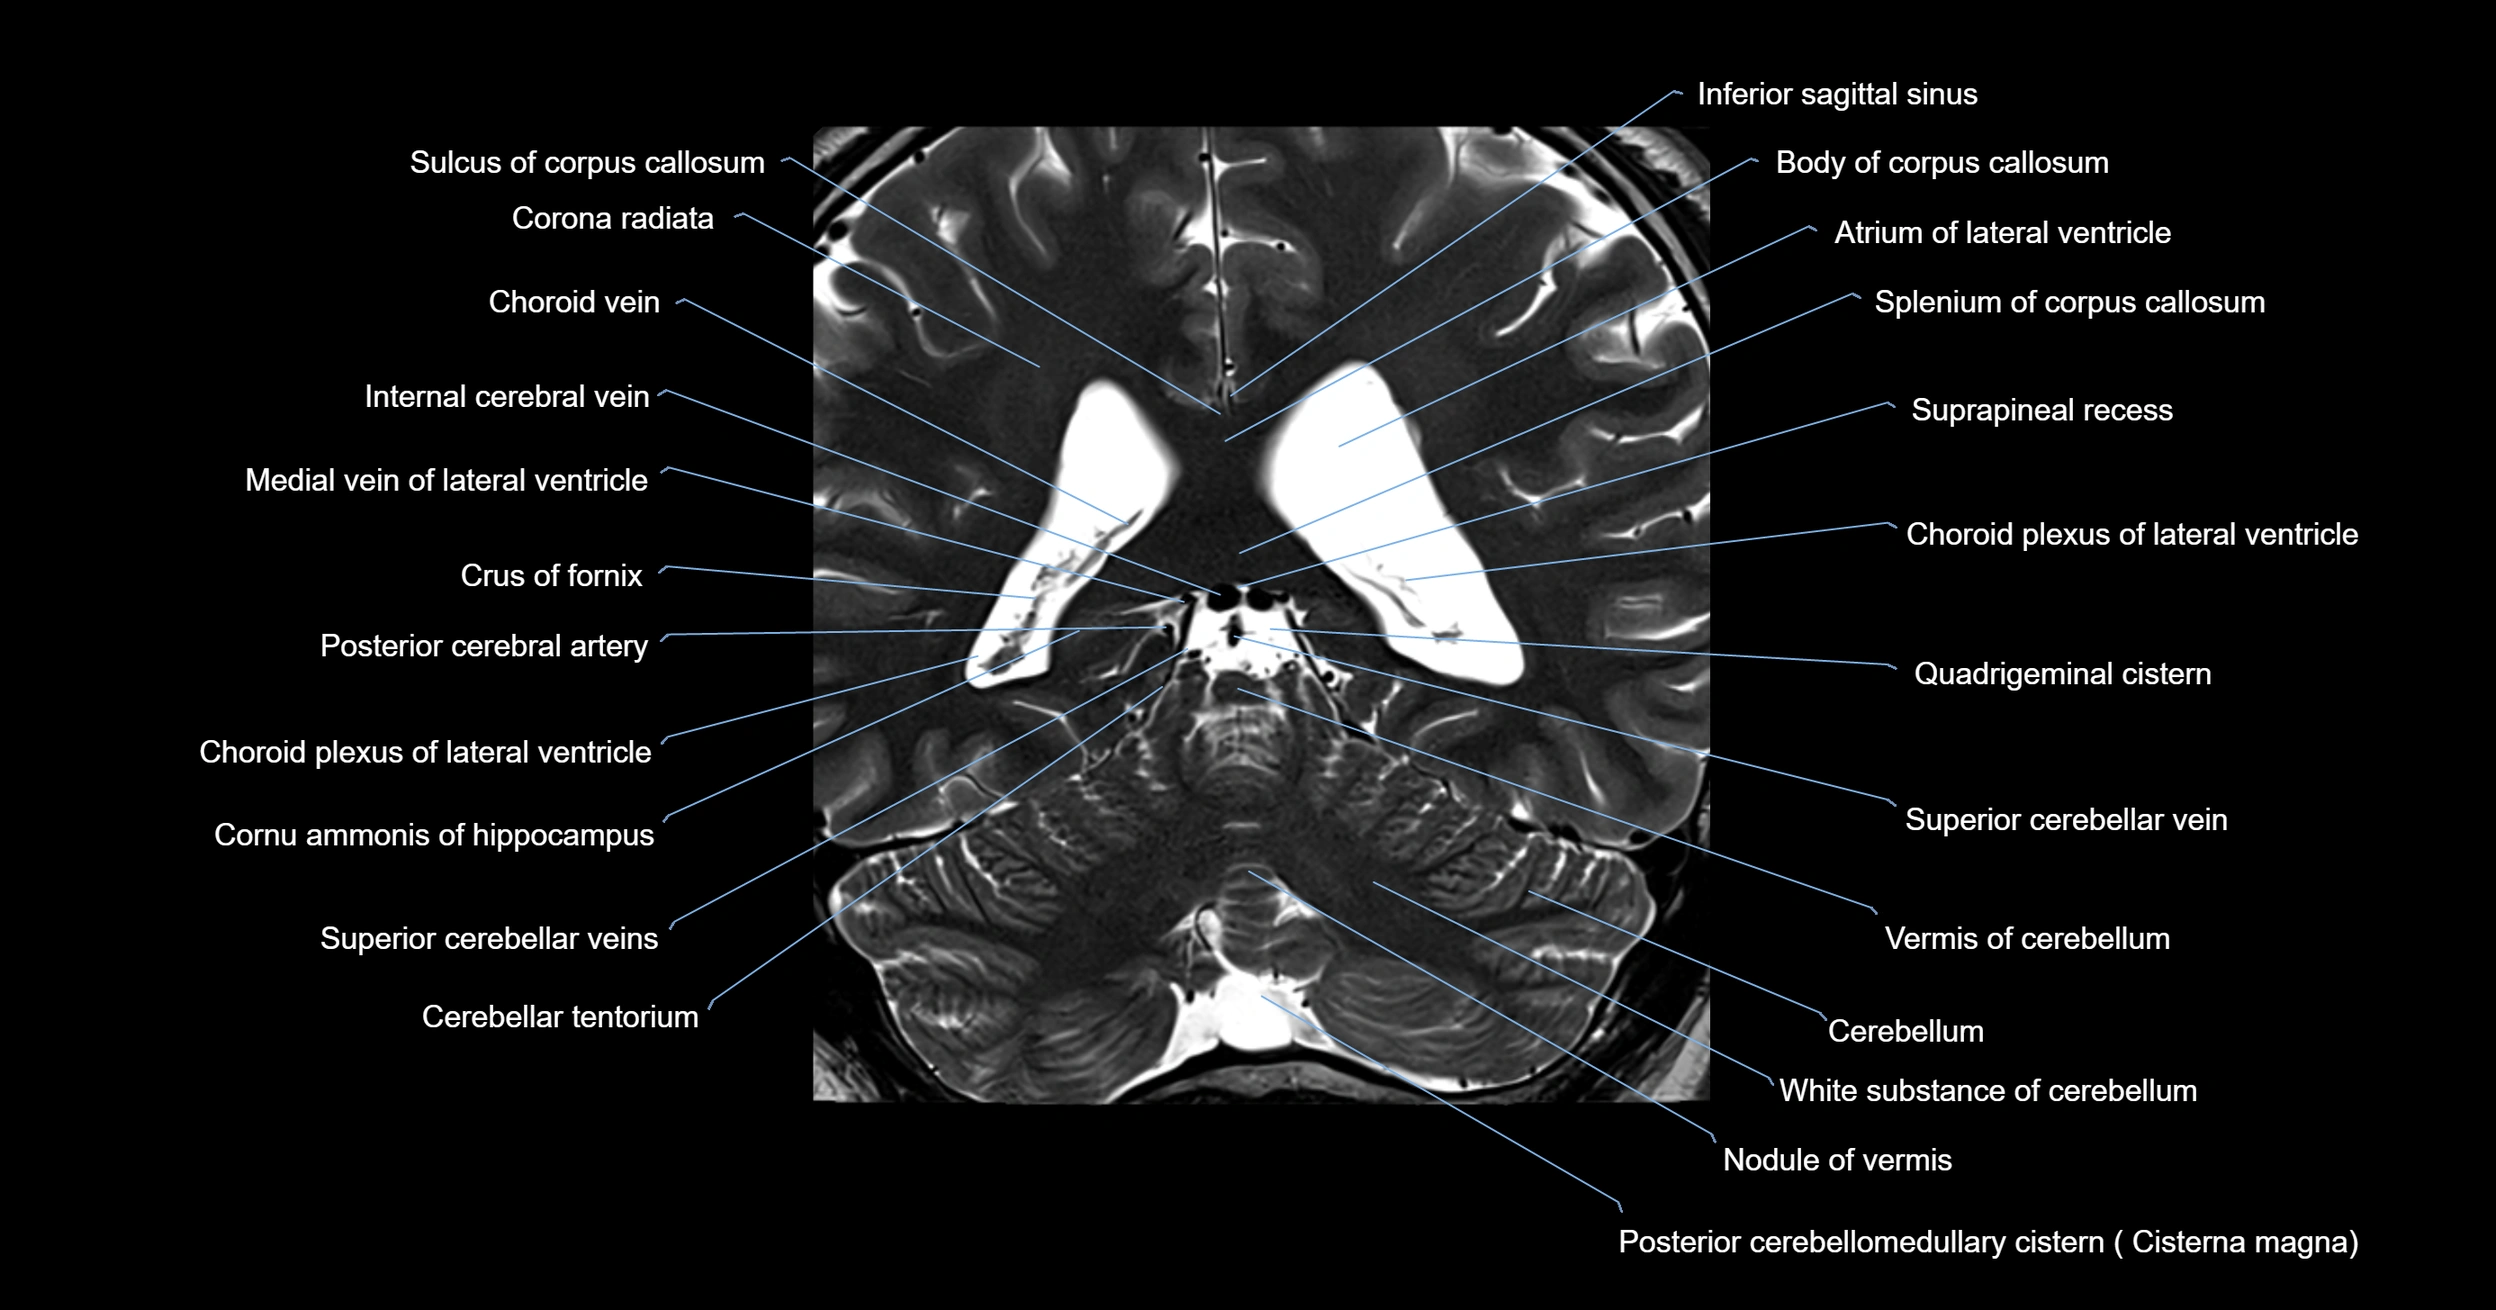

MRI images